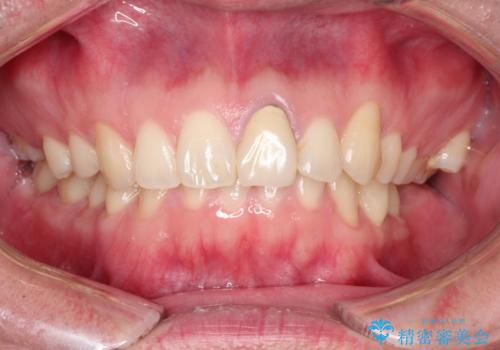

前歯が黒くなってきた。オールセラミッククラウン

- 前歯の変色を主訴に来院されました。

根管治療は希望されなかったので、リスクを説明した上でオールセラミッククラウンの治療を行っています。

金属の被せ物は歯肉の変色を起こしやすくなります。オールセラミッククラウンは金属を使わないため審美的な治療を行うことができます。